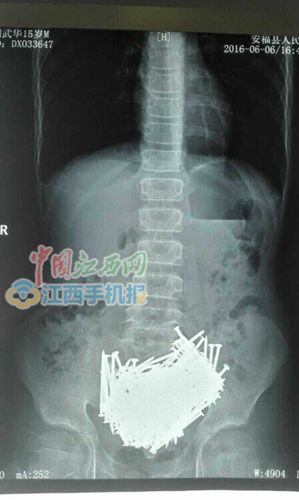

CT检查结果

中国江西网吉安讯 近日,中国江西网记者获悉,安福县金田乡15岁少年小刘,因身体不适被家人送医检查,CT检查后惊呆了医生,胃里一堆钉子,手术后取出200多颗钉子,还有牙签、石头、硬币等,共重约700克。